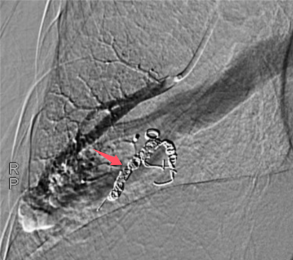

患者,男,61岁,近三年来反复因头晕、呼吸困难、血红蛋白异常增高,辗转于重庆市多家医疗机构治疗,考虑红细胞增多症,并多次行放血治疗,治疗效果不佳,遂来我院呼吸与危重症医学科门诊就诊。副院长刘碧翠主任医师结合患者的结果,以及肺部CT多发团块影,高度怀疑为动静脉瘘引起血红蛋白异常升高,遂收住院进一步检查。入院后,通过支气管动脉CTA检查,确诊为肺动静脉瘘。呼吸与危重症医学科李奎副主任医师遂带领血管介入团队经过术前认真讨论,严密制定了手术计划,征得患者及家属同意后,完成了经皮肺动脉造影加双侧肺动脉栓塞术。术中患者氧饱和度在不吸氧的情况下从80%立即提升至95%,手术效果显著,术后恢复良好,顺利出院。

李奎副主任医师指出:“肺动静脉瘘是一种罕见的肺部血管疾病,表现为肺动脉血液绕过肺泡直接流入肺静脉,形成短路,导致发绀、胸闷、气短等症状。肺动脉栓塞术是一种微创治疗方法,通过精准的血管封堵,有效治疗这一疾病。”